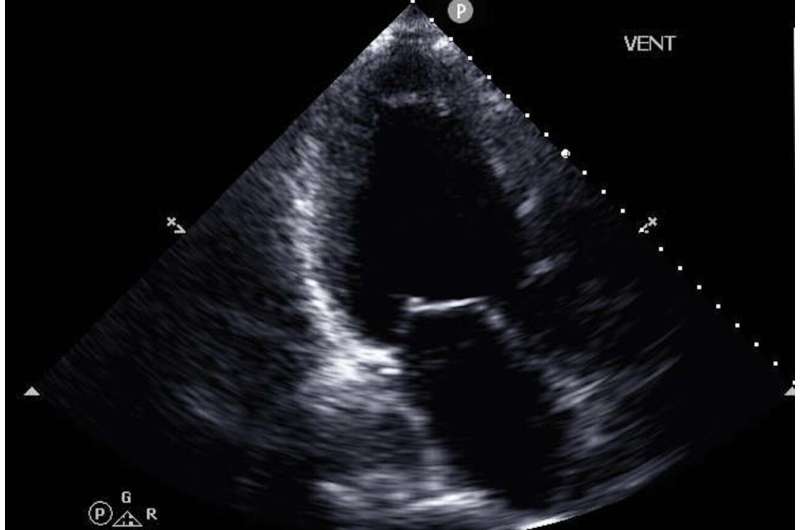

In the new study, published March 3 in npj Digital Medicine, the researchers tested a novel AI-powered method that may remove this bottleneck. The new method predicts with high accuracy the most important CPET measure, peak oxygen consumption (peak VO2), using much more easily obtainable ultrasound images of the patient’s heart plus the patient’s electronic health records.